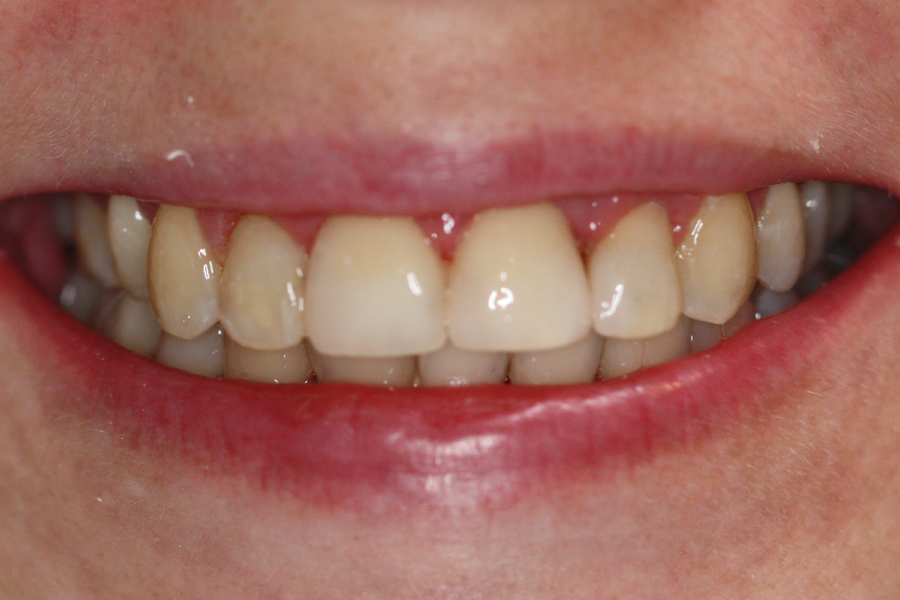

Kompleksowe leczenie zachowawczo-ortodontyczne

Młoda pacjentka zgłosiła się do naszego gabinetu celem wykonania kompleksowego leczenia zachowawczo-ortodontycznego. Oprócz problemów natury ortodontycznej stwierdzono złą higienę jamy ustnej oraz liczne potrzeby leczenia zachowawczo-endodontycznego. Po wnikliwej analizie telerentgenowskiej oraz analizie modeli zadecydowano o ekstrakcji 2 zębów w łuku dolnym (kła po stronie lewej oraz pierwszego przedtrzonowca po stronie prawej). Plan leczenia obejmował ponadto zamknięcie łuku po brakujących zębach w łuku górnym. Leczenie aktywne trwało 2 lata i 8 miesięcy. W czasie jego trwania pacjentka była regularnie poddawana zabiegom higieny profesjonalnej celem eliminacji zapaleń przyzębia brzeżnego. Po leczeniu aktywnym zastosowano leczenie retencyjne w postaci retainera stałego w żuchwie oraz szyny retencyjnej w łuku górnym.